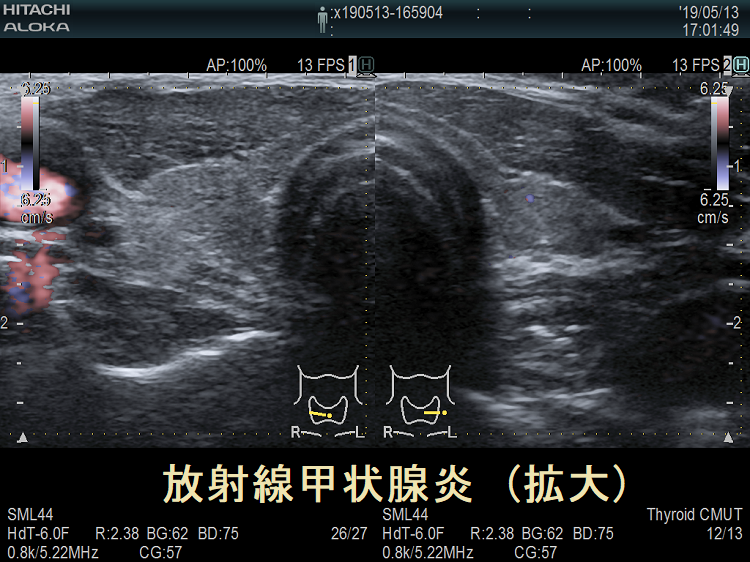

子宮頸がん頸部リンパ節転移に放射線外照射した後の放射線甲状腺炎 超音波(エコー)画像 超音波(エコー)画像 (拡大);内部は等エコー、比較的均一。